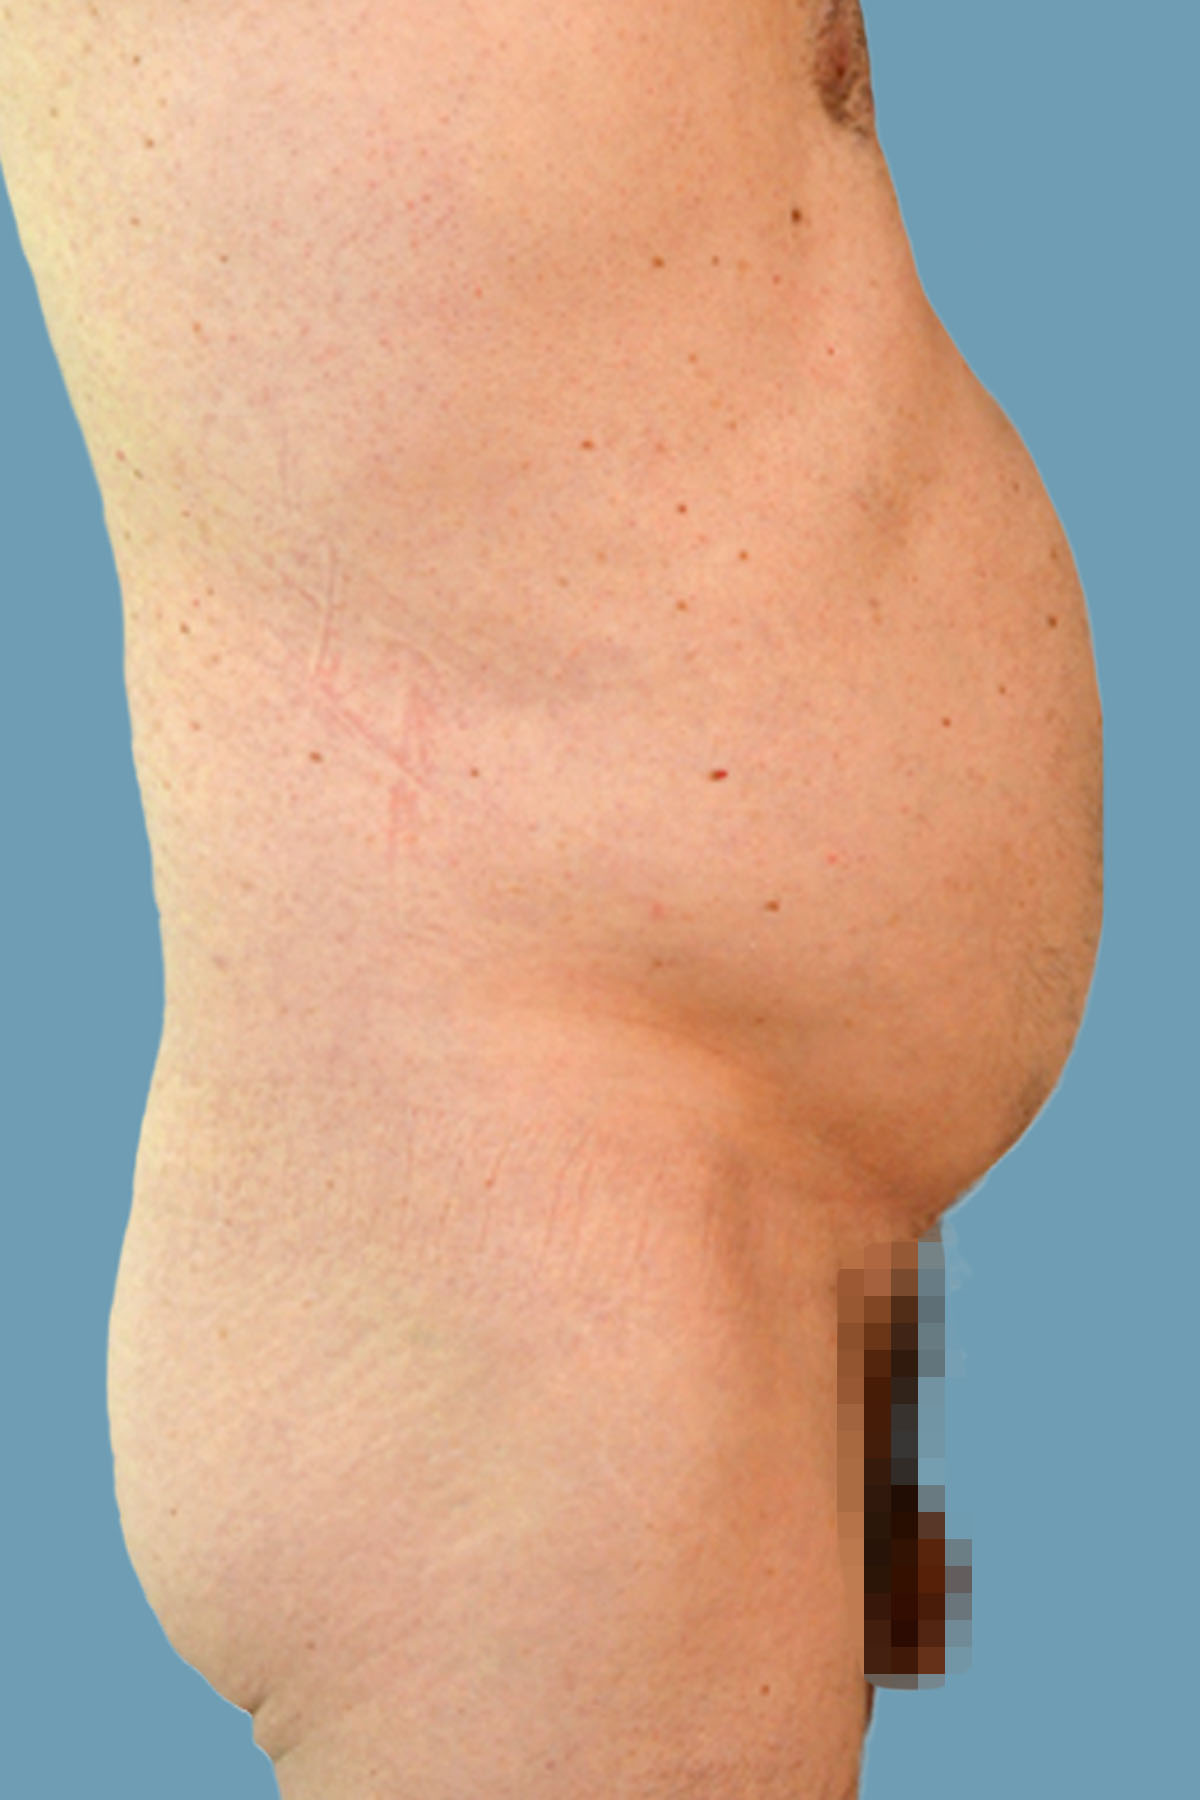

Figure 12. Case 2: Middle-aged man who exercised moderately. He presented with no midline abdominal or umbilical hernias. There was evidence of bulging abdominal wall.

Figure 13. Case 2: Postoperative front view shows improvement of contour with reduction of the global abdominal wall distention.

Figure 14. Case 2: Preoperative lateral view shows the global abdominal wall distention.

Figure 15. Case 2: Postoperative lateral view shows the significant clinical improvement in the abdominal wall protuberance. Comparative pre- and postoperative magnetic resonance imaging is shown in Figures 24 and 25.